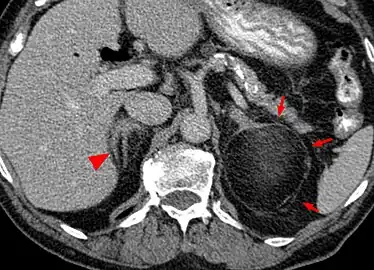

Myeloplipoma shown on a CT scan image

Most myelolipomas are unexpected findings on CT scans and MRI scans of the abdomen. They may sometimes be seen on a plain X-ray films.[4]